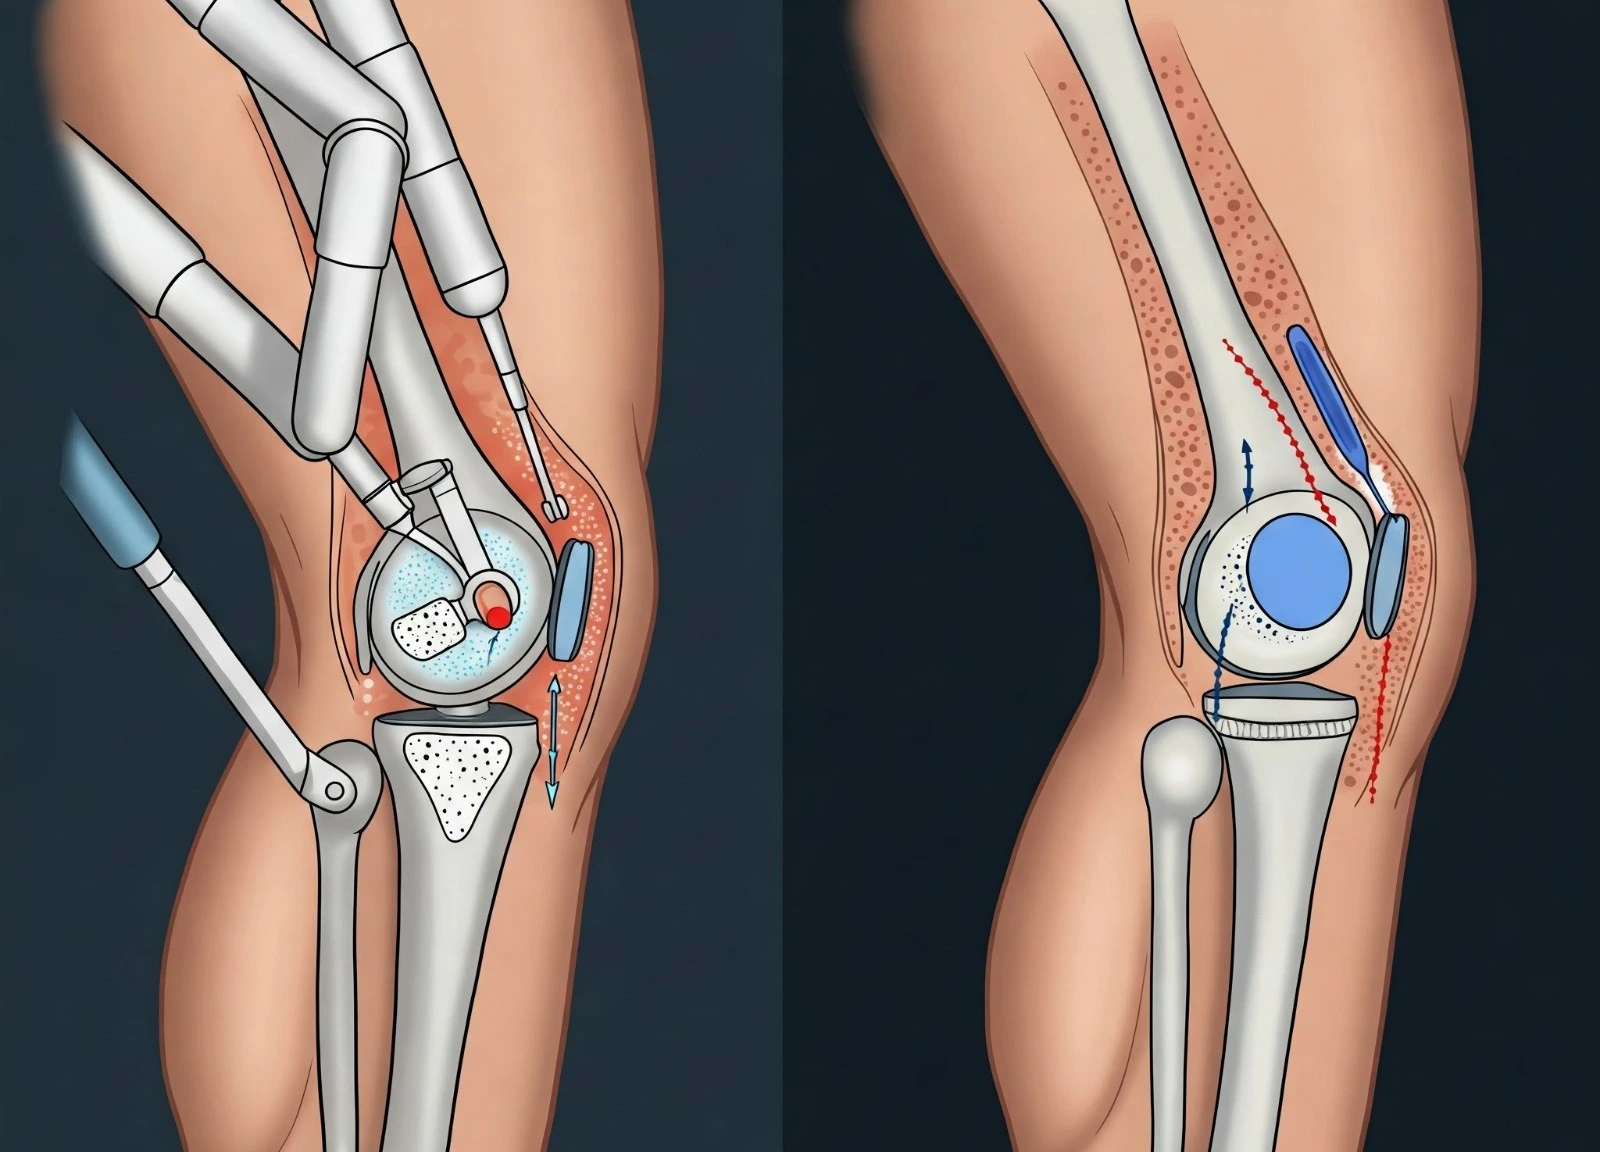

Robotic & Conventional Joint Replacement